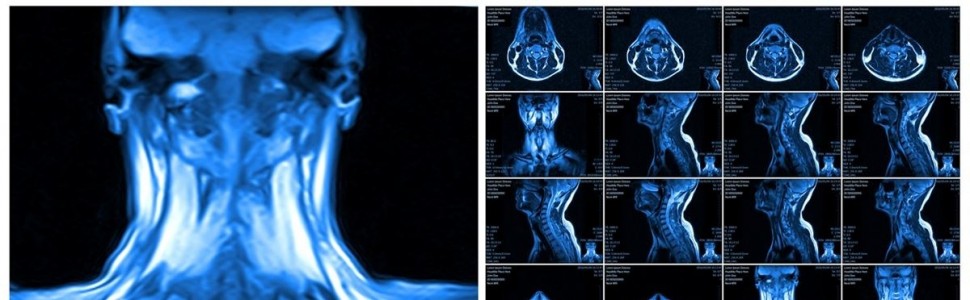

3. Jeśli nawet aparat ortodontyczny czy retainer nie jest wykonany ze stopów o właściwościach ferromagnetycznych, to i tak w badaniu MR metale powodują powstanie artefaktów o różnym nasileniu, które są ograniczone do okolicy głowy. Jeżeli są badane inne okolice ciała pacjenta, artefakty te nie obniżają jakości obrazu. Ponadto istnieją techniczne możliwości redukcji artefaktów przez unikanie niektórych sekwencji akwizycji obrazu i/lub zastosowanie obrazowania w innych płaszczyznach.